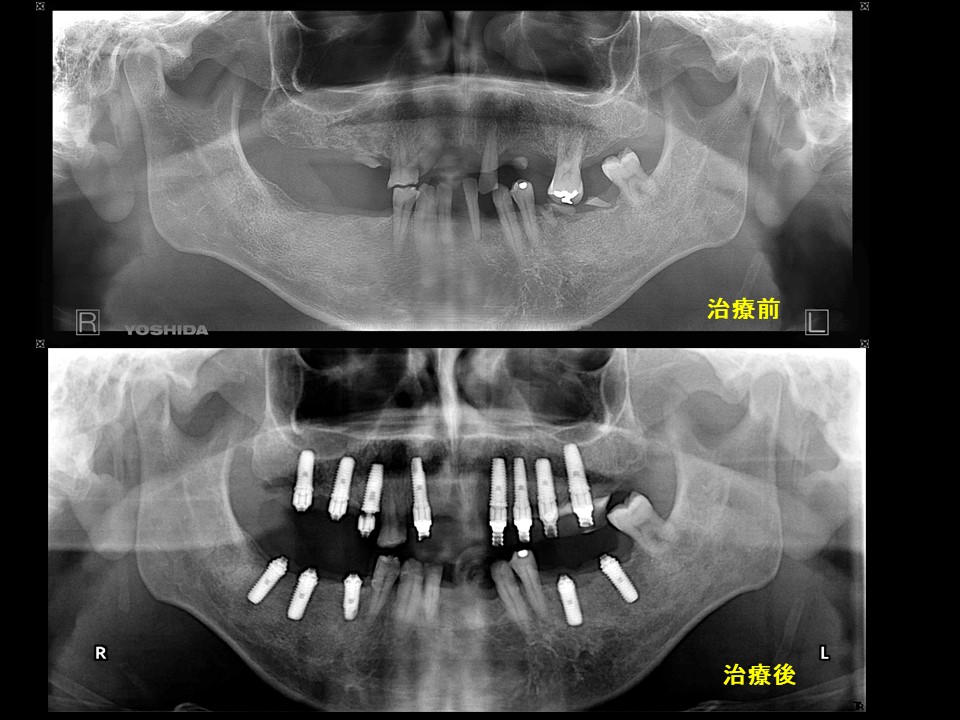

症例4